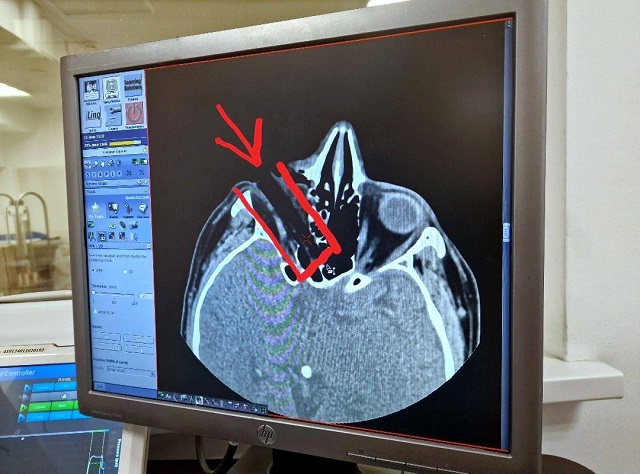

Диагноз: «Проникающая рана глазницы с наличием инородного тела», «Смещение глазного яблока», острота зрения — 0%. Результат компьютерной томографии неутешительный: частичное повреждение глазного нерва, инородное тело размером 7 на 1,5 см вошло под нижним веком и застряло буквально в 8 мм у основания черепа.

Врач-офтальмолог Булат Шайдуллин объяснил, что при первичном осмотре уже было понятно, что случай очень сложный: глаза под веком вообще не было видно. Глазное яблоко сместилось выше под надбровные дуги. Пациент был экстренно взят на операцию.